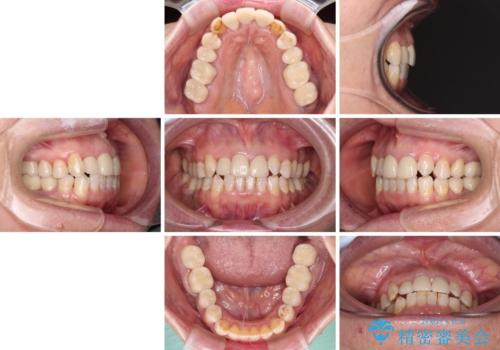

- 全顎的な歯列不正と、銀歯だらけの奥歯を気にして来院された患者様です。

奥歯の銀歯は、セラミッククラウンを装着するには歯の高さが不十分であり、そのままでは矯正治療を行うことが困難であるため、歯冠長延長術を行うこととしました。

また、根管治療の必要な歯がいくつかあるため、歯周外科治療の治癒期間を利用して根管治療を行い、その後インビザラインにて矯正治療を行うこととしました。

矯正治療後にはオールセラミッククラウンにて補綴治療を行うこととしました。

歯冠長延長術を行ったことで、自然な形態かつ清掃性の高いセラミッククラウンを装着することができました。

全顎的に治療を行ったため、治療期間も費用も負担は大きくなりましたが、統一感のある仕上がりとなりました。